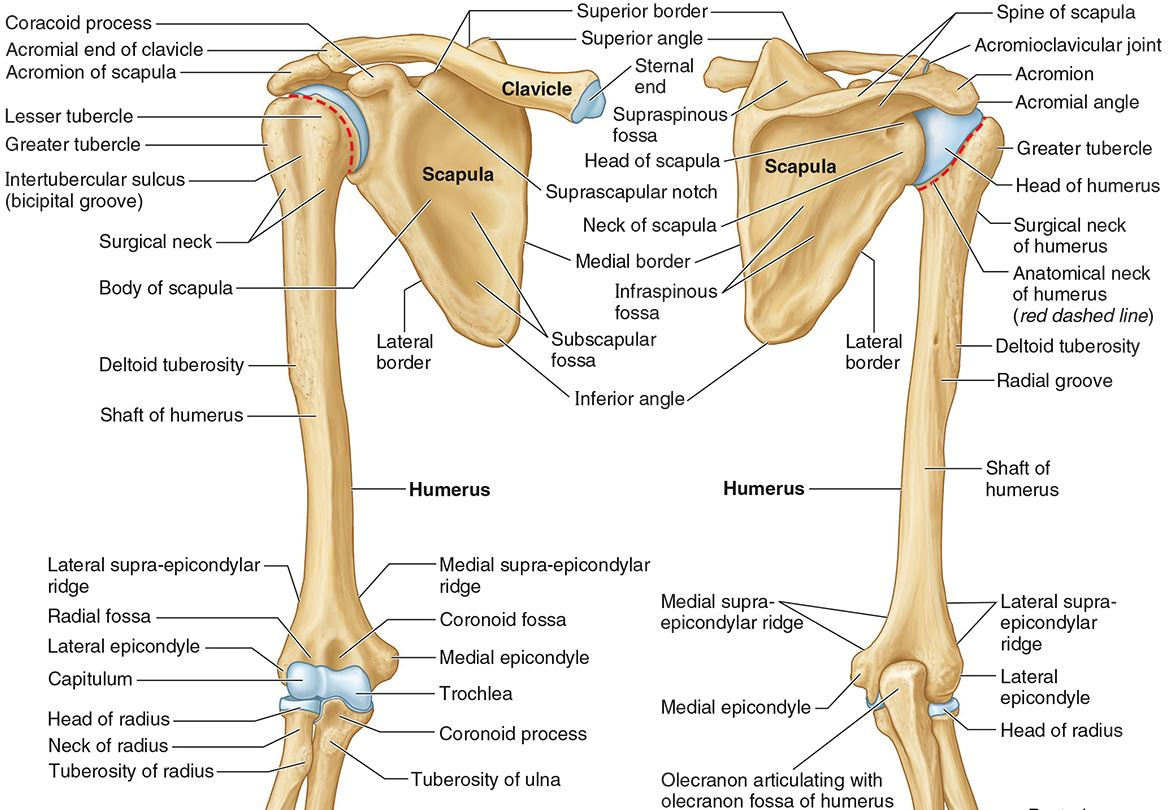

What part of the humerus is this?

The head of the humerus articulates with the scapula at the glenohumeral joint.

What part of the humerus is this?

The anatomic neck is an indentation distal to the head and provides an attachment for the fibrous joint capsule of the glenohumeral joint.

What part of the humerus is this?

The greater tubercle lies lateral and distal to the anatomic neck.

What part of the humerus is this?

The lesser tubercle lies on the anterior/medial side of the humerus, just distal the anatomic neck.

What part of the humerus is this?

The intertubercular (bicipital) groove lies between the greater and lesser tubercles.

What part of the humerus is this?

The surgical neck is a narrow area distal to the tubercles. It is a common site for proximal humerus fractures.

What part of the humerus is this?

The humeral shaft features the deltoid tuberosity laterally for the distal insertion of the deltoid muscle.

What part of the humerus is this?

The radial groove is an oblique depression that contains the radial nerve and deep brachial artery.

Which parts of the humerus is this?

The medial and lateral epicondyles are distal prominences to which many forearm tendons attach, near the elbow joint.

Which parts of the humerus is this?

The medial and lateral supracondylar ridges extend superiorly from the medial and lateral epicondyles.

Which parts of the humerus is this?

The trochlea and the capitulum (the condyles) are the most distal surfaces of the humerus, where it articulates with the forearm bones at the elbow joint

What part of the humerus is this?

The olecranon fossa is a posterior depression above the trochlea that receives that olecranon process of the ulna

What part of the humerus is this?

The coronoid fossa is an anterior depression above the trochlea that receives that coronoid process of the ulna.